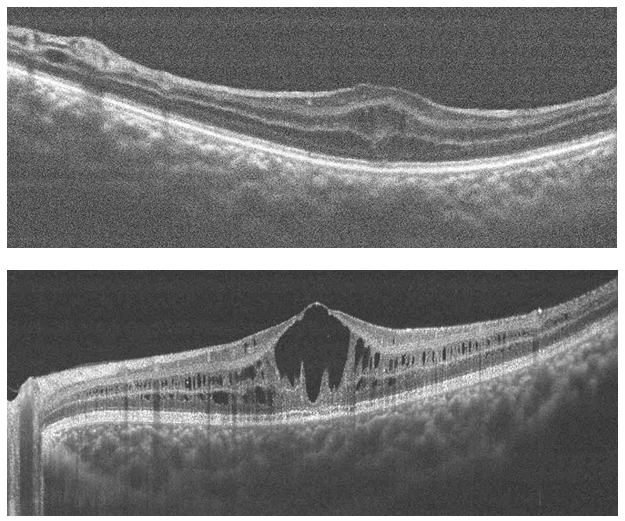

Optical coherence tomography is a non-invasive diagnostic technique that allows morphological and quantitative analysis of living tissue with an axial resolution of nearly 10 microns.8 Studies have demonstrated that OCT imaging show a wide assortment of finding in regards to retinoschisis patients, especially when describing cystoid macular changes.2,9−11 The classic OCT image is described as cavitations compromising the neurosensory retina from its internal to its outer layers with thin septa connecting both layers as previously described by others (Figure 3).1,12−14

Figure 3 (Top) Right Eye and (Bottom) Left Eye Cross Line OCT. Cyst like cavities splitting retina layers.